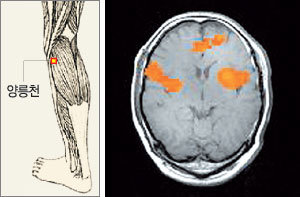

양릉천혈에 침을 놓은 후의 뇌 사진. 정확하게 침을 놓았을 때는 뇌의 운동피질이 활성화되었다.-사진제공 전신수 교수

▽마비, 침술로 풀 수 있다=현대의학의 관점에서는 손발은 뇌의 운동피질에서 내린 명령에 따라 움직인다. 반대로 손발에 자극을 줬다 해서 뇌의 운동피질이 활성화되지는 않는다. 그러나 이번 연구에서 침으로 정확하게 자극하면 뇌의 운동피질이 활성화되는 것으로 확인됐다.

연구팀은 2001년 2월부터 지난해 12월까지 20명을 두 그룹으로 나눠 A그룹에는 뇌중풍 마비 치료효과가 가장 높은 양릉천(陽陵泉)혈에 침을 놓고 B그룹에는 양릉천혈 주위에 침을 놓은 뒤 기능성자기공명영상(f-MRI)으로 뇌를 촬영했다. 그 결과 A그룹은 모두 뇌의 운동피질이 활성화된 반면 B그룹은 아무런 변화가 없었다. ▽한방 과학화, 돛 올렸다=동물실험에서 경락이 확인된 적은 있지만 실제 사람에게서 경락과 경혈의 존재가 입증된 것은 이번이 처음이다. 또 반쪽 마비가 올 때 마비가 없는 반대쪽 팔다리에 침을 놓는다는 동의보감의 내용이 과학적으로 타당하다는 것도 이번에 확인됐다.

이번 연구결과 왼쪽 다리의 양릉천혈에 침을 놓으면 왼쪽 뇌의 운동피질이 활성화됐다. 과학적으로 왼쪽 뇌는 인체의 오른쪽을 지배한다. 따라서 왼쪽 뇌가 활성화되면 인체의 오른쪽 운동기능이 개선되는 것이다. 결국 마비된 반대쪽에 침을 놓는, 그동안의 침술치료법이 과학적 근거를 갖게 된 셈이다.